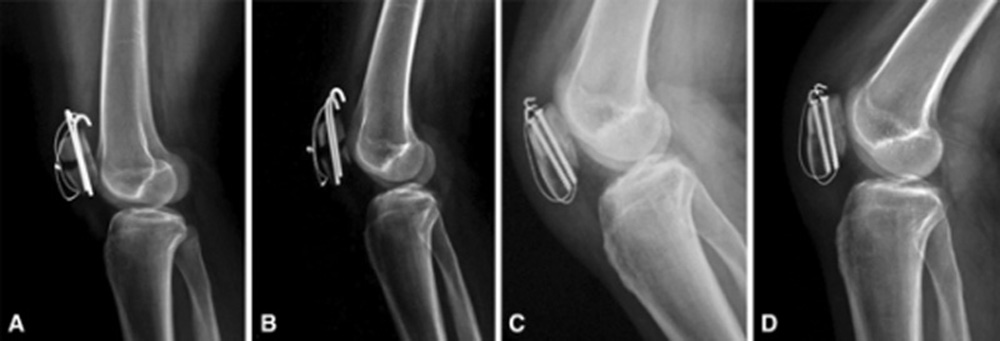

ممکن است با استفاده از روش های غیر جراحی و یا جراحی انجام شود .در صورتیکه قطعات شکسته شده بدون جابجایی باشند درمان غیر جراحی است. به این صورت که پزشک معالج ابتدا خون داخل زانو را با سرنگ خارج کرده و سپس با استفاده از گچ بلند اندام تحتانی، زانو را یک و نیم ماه در حالت راست و مستقیم نگه داشته تا استخوان های شکسته شده جوش بخورند. اما اگر قطعات شکسته شده از هم جدا شده باشند بیمار نیاز به عمل جراحی دارد به این معنی که پزشک در اطاق عمل پوست را برش میدهد و در زیر آن استخوان شکسته شده کشکک نمایان میشود. جراح سپس قطعات شکسته شده را با ابزارهای بخصوصی در کنار یکدیگر قرار داده و سپس به توسط پین و سیم های فولادی آنها را در کنار یکدیگر محکم میکند.

گاهی اوقات استخوان در محل اتصال به تاندون های بالا و یا پایین خود دچار شکستگی خرد شده و چند تکه میشود. در این حال ممکن است پزشک معالج تکه های خرد شده را پرت داده و تاندون را به قسمت باقیمانده کشکک متصل کند. گاهی وسط کشکک بشدت خرد شده است. در این حالات جراح ممکن است این قطعات ریز و خرد شده را پرت داده و دو قطعه بزرگ و عمده بالا و پایین را به یکدیگر متصل کند . بندرت در شکستگی های بسیار خرد شده کل کشکک، پزشک ارتوپد مجبور میشود تمام قطعات خرد شده یعنی تمام کشکک را پرت داده و تاندون های چهارسر در بالا را به تاندون کشکک در پایین متصل کند .